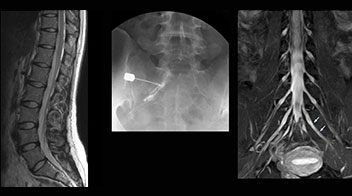

At Northern Fukushima Medical Center in Japan, excellent MRI visualization of nerves helps support confident diagnoses and informs surgical treatment decisions for patients with lower limb symptoms. MRI technologist Tanji and orthopedic surgeon Dr. Yabuki share how direct nerve visualization with the 3D NerveVIEW method adds information when diagnosing atypical herniations. The additional insights changed their way of working and benefit their patient care, as illustrated by some clinical examples.

“In patients with lower extremity neurological symptoms, NerveVIEW helps us to determine the disease matching the patient’s symptoms by directly visualizing the nerves. We use the sequence mainly, when there is suspicion of intraforaminal stenosis, extraforaminal stenosis or lateral disc herniation, which is often based on routine T2- and T1-weighted images. Additionally, the excellent depiction of the course of nerves makes NerveVIEW a good navigator when applying treatment such as block therapy or surgery.”

“In such case, we would then browse through axial T2-weighted MR images slice by slice and mentally reconstruct the actual situation based on both radiculography and MRI. Fortunately, NerveVIEW can now very well show nerve courses and presence of nerve compression or edema in one single image series.” “We have often seen NerveVIEW directly depict details of the nerve compression that were not observed by radiculography. Therefore, we think that with NerveVIEW we can reduce the number of invasive examinations, especially for some patients with lumbar plexus symptoms.”

“Before NerveVIEW, diagnosis by MRI alone was sometimes difficult, unless there was a strong suspicion based on clinical symptoms,” says Shoji Yabuki, MD, DMSc, Orthopedic surgeon at Fukushima Medical University School of Medicine. “This is why we routinely perform selective lumbosacral radiculography (nerve root block) and x-ray in such cases. However, radiculography can only depict nerves as far as the contrast agent reaches. When a nerve is distorted by compression, the contrast agent will not pass through this compressed area, preventing us from evaluating the full nerve compression.”

“Although symptoms of typical disc herniation and atypical hernia are very similar, the actual site of herniation is different. It is therefore important to characterize the nerve’s condition both inside and outside of the intervertebral foramina. “Conversely, if we see no abnormality in NerveVIEW, we can assume at least that there is no severe condition that requires surgery. Like this, it can help us avoid unnecessary surgery. NerveVIEW can have a tremendous impact in this way.”

“NerveVIEW is really useful for those cases where a nerve disorder is strongly suspected based on the clinical examination but our regular MRI images do not show any findings. These atypical herniations and spinal canal stenosis, occurring in 5% to 15% of the total lumbar herniation/stenosis cases are our main target when using NerveVIEW,” says Dr. Yabuki.